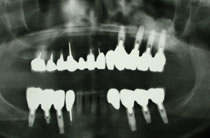

60代女性のインプラント治療例2